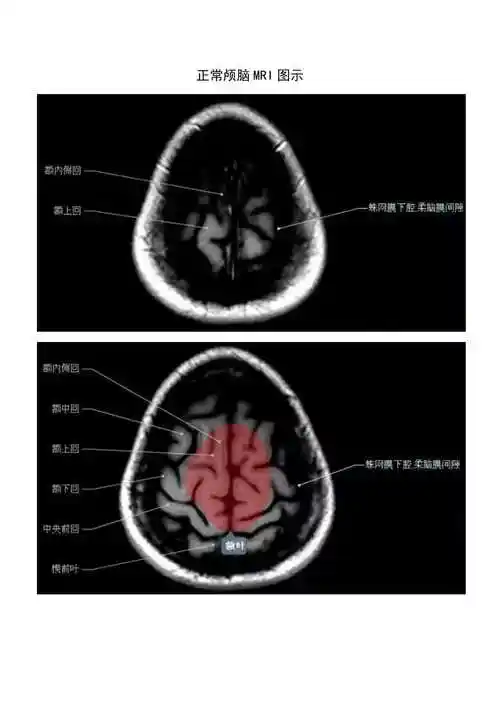

高清mri图颅脑磁共振mri解剖

正常颅脑磁共振图示docx

解剖颅脑丨高清头颅mri断层解剖图谱